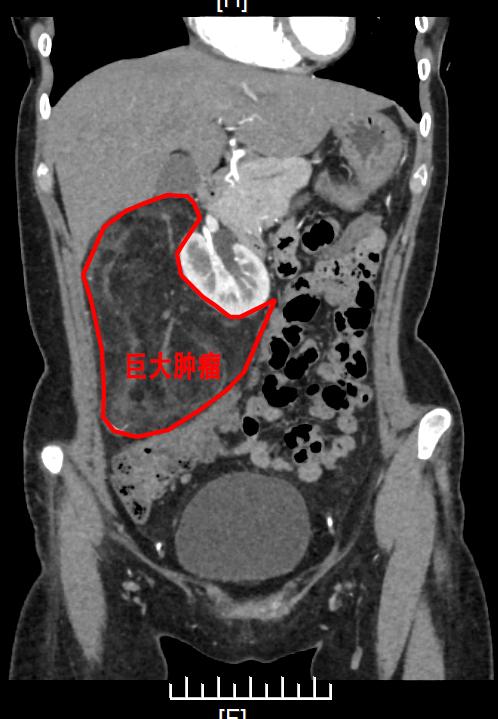

入院后,经增强CT提示右侧腹膜后巨大富脂肪肿瘤,肿瘤上界达右侧膈下,下界至盆腔,几乎占据整个右侧腹膜后间隙,考虑为血管平滑肌脂肪瘤。尽管该肿瘤为良性肿瘤,但体积如此之大并不常见,如行开腹手术则手术切口可长达30cm以上,对患者创伤大,且术后恢复慢、疼痛明显。鉴于患者为年轻女性,经充分考虑后,我院季惠翔教授、支轶教授决定行经腹腹腔镜腹膜后肿瘤切除术,并制定了周密的手术方案。